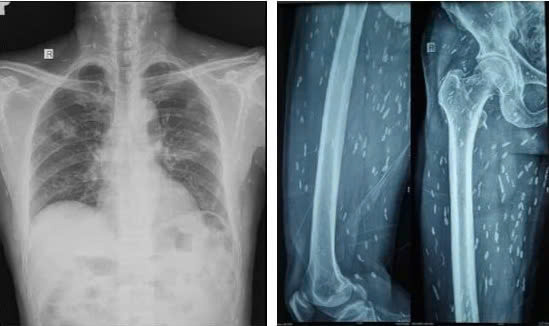

| Sán xuất hiện khắp cơ thể người bệnh. Ảnh: BVCC. |

Bệnh nhân được chụp Xquang xương đùi, CT-scan ngực để tầm soát tổn thương ở cơ quan khác, phát hiện vô số nang sán dải còn sống hoặc đã bị hóa vôi “ẩn nấp” trong não, nhu mô phổi, và trong da, cơ trên toàn bộ cơ thể người bệnh.